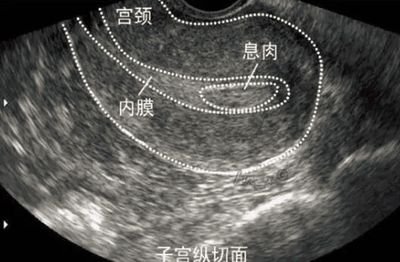

2. 子宫内膜容受性差

子宫内膜是胚胎着床的“土壤”。如果内膜过薄、形态不佳、存在息肉、粘连或慢性炎症等问题,即使移植优质胚胎,也可能无法成功着床。此外,免疫因素、凝血功能异常等也可能影响内膜的接受能力。